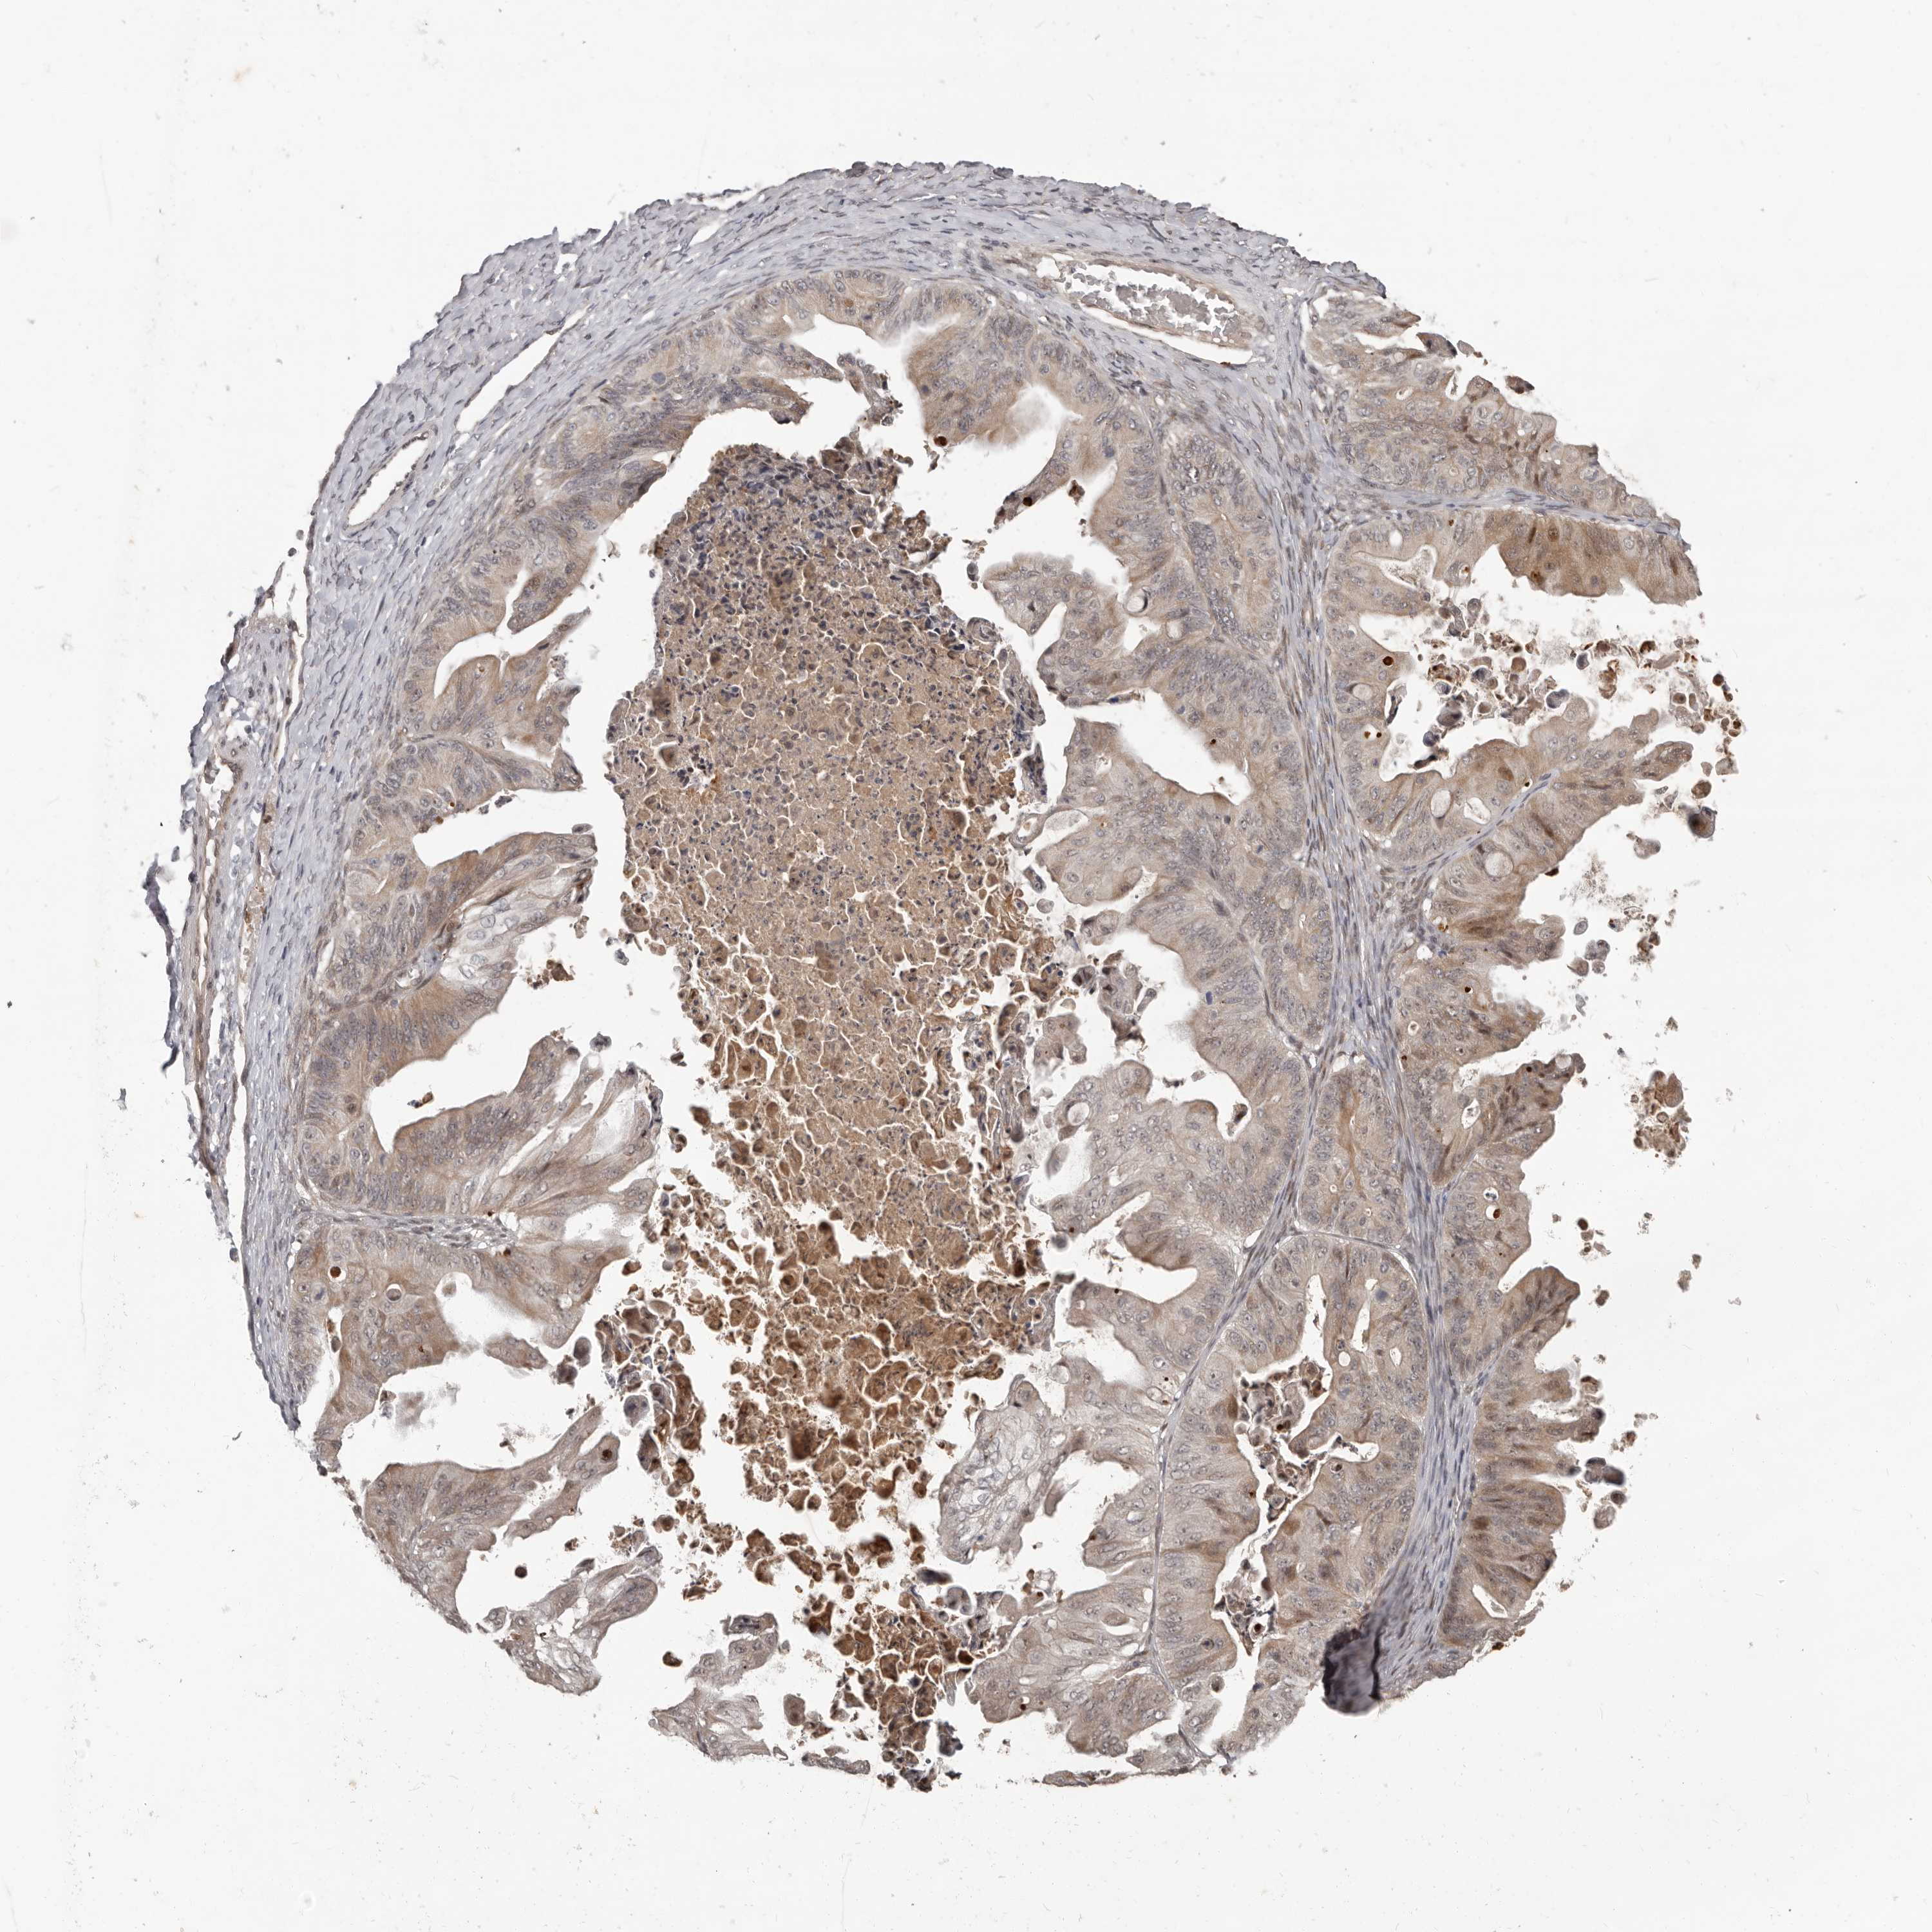

OVARIAN CANCER - Protein expressioni

A mouse-over function shows sample information and annotation data. Click on an image to view it in a full screen mode. Samples can be filtered based on level of antibody staining by selecting one or several of the following categories: high, medium, low and not detected. The assay and annotation is described here.

Note that samples used for immunohistochemistry by the Human Protein Atlas do not correspond to samples in the TCGA dataset.

Antibody stainingi

Antibody staining in the annotated cell types in the current human tissue is reported as not detected, low, medium, or high, based on conventional immunohistochemistry profiling in selected tissues. This score is based on the combination of the staining intensity and fraction of stained cells.

Each image is clickable and will lead to virtual microscopy that enables deeper exploration of all samples and also displays staining intensity scores, fraction scores and subcellular localization as well as patient and tissue information for each sample.

Antibody HPA029165

Antibody HPA029167

Antibody CAB028574

Cystadenocarcinoma, serous, NOS

Carcinoma, endometroid

Cystadenocarcinoma, mucinous, NOS

Carcinoma, NOS